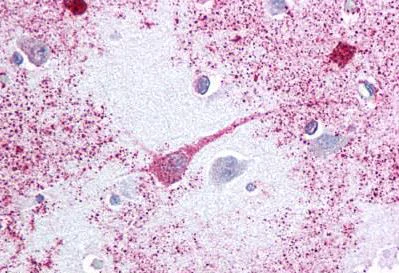

Immunohistochemistry (Formalin/PFA-fixed paraffin-embedded sections) - Anti-PTGER3 antibody - Cytoplasmic domain (AB189122)

Immunohistochemical analysis of formalin-fixed, paraffin-embedded human brain cortex tissue labeling PTGER3 with ab189122 at 2 μg/ml.